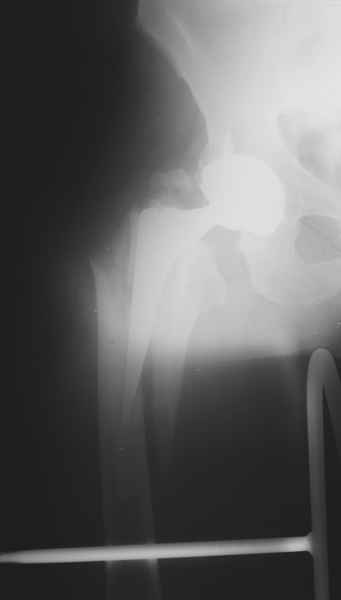

2. Применение ножки дистальной фиксации, мы отдаем предпочтение ножке Вагнера с фиксацией проксимального отдела на ножке. Более травматичное вмешательство, но при стабильной фиксации ножки реабилитация идет в обычном режиме.

Хочется показать два подобных случая, П-ка З. 72 лет и п-т Г. 80 лет. Сразу принимаю замечание, что это были ножки цементной фиксации, просто под руками не было бесцементника.